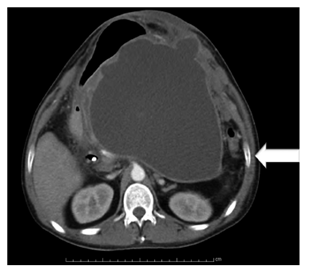

Se incluyeron 10 pacientes con diagnóstico de pseudoquiste pancreático (Figura 1) a quienes se les realizó drenaje transmural por ecoendoscopia. Las variables demográficas principales se presentan en la Tabla 1.

5 pacientes eran mujeres (50%). El rango de edad de presentación estaba entre 11 y 68 años de edad. El diámetro promedio fue 10,6 cm (5-22 cm). El 90% de los casos comprometía el cuerpo de páncreas. Se logró implantar exitosamente un stent transmural (cistogastrostomía) en 9 pacientes (90%) (Figura 2), en 6 pacientes se colocó solo el stent metálico autoexpandible parcial o totalmente recubierto y en 3 pacientes se colocó el stent metálico y en su interior un stent doble cola de cerdo de 10 Fr, en 1 paciente se realizó el drenaje por aspiración con resolución del 95% del tamaño de la lesión dado que el pseudoquiste fue de 5 cm. Un paciente presentó durante el procedimiento liberación del stent metálico dentro de la cavidad del pseudoquiste, requirió la colocación de otro stent metálico y en un segundo tiempo endoscópico, 48 horas después, se retiró el stent entrando a la cavidad con un endoscopio pediátrico y luego se reposicionó el stent migrado.